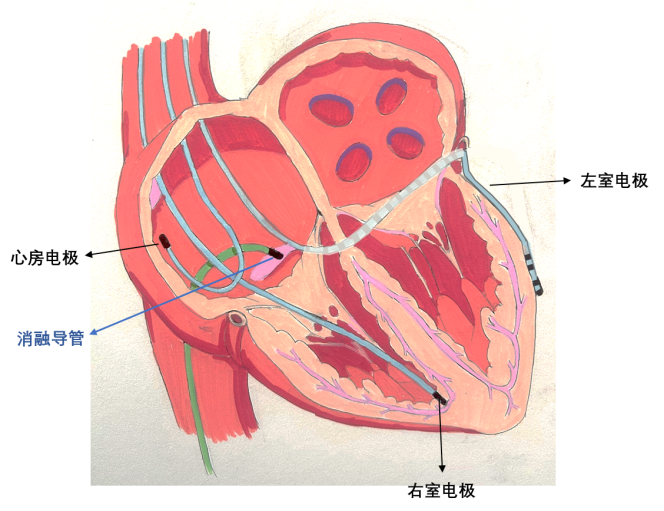

一、什么是房室结消融联合起搏器植入术?

它是由两个手术组成,一个是起搏器植入术,包括普通双腔、CRT(三腔)起搏器的植入。另一个手术是消融房室结(或房室交界区),目的是阻断房室之间的电连接,从而令快速紊乱的房性心律不影响心室的收缩。